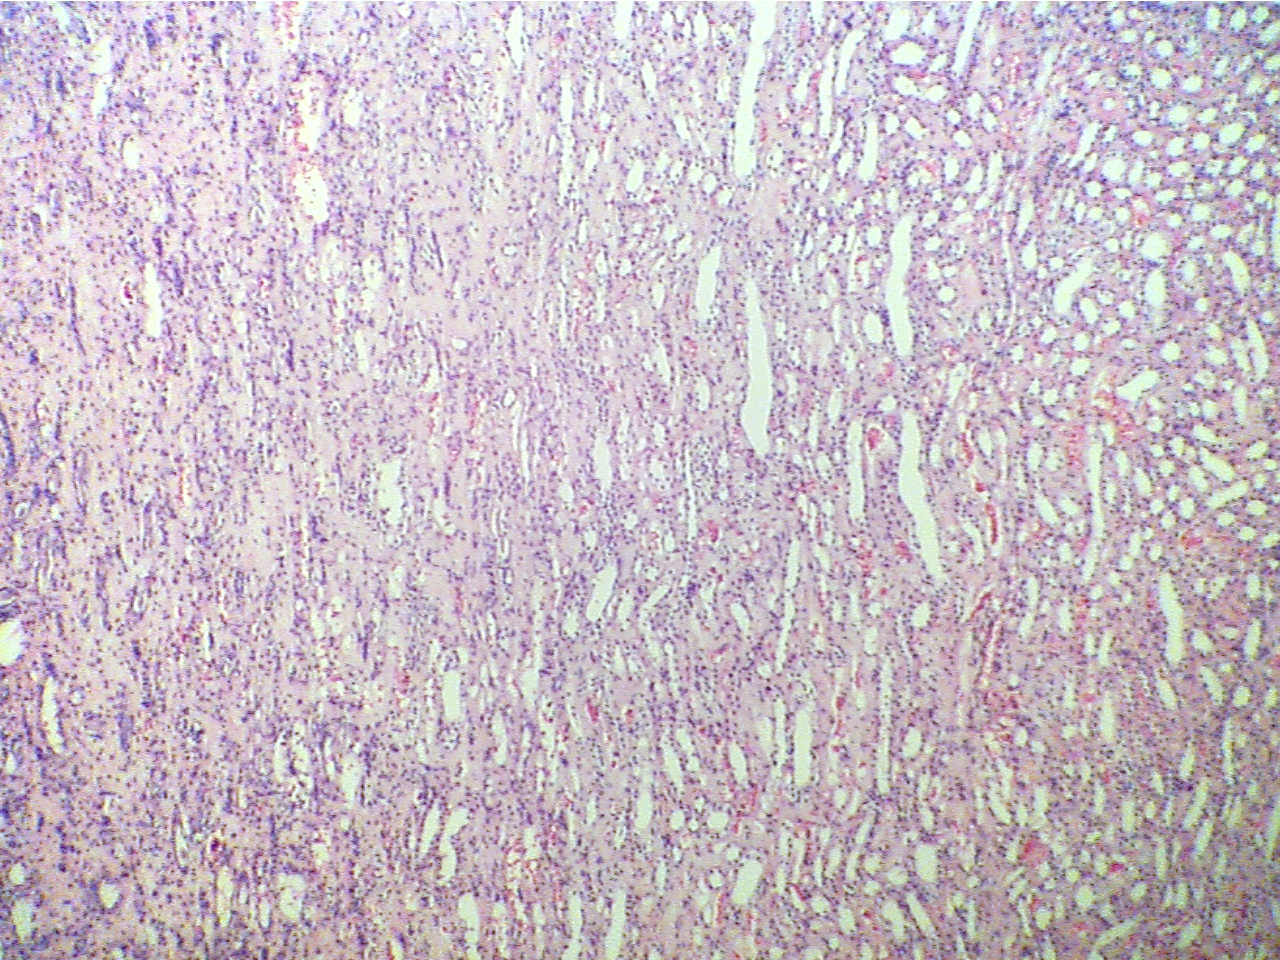

Note that tubular cells have undergone extensive proliferation and have lost

their characteristic appearance. They look more like undifferentiated cells and

there is extensive stroma filled with red blood cells between the cancer cells.

See Fig. 8-9. This situation is very different from that of the benign adenoma

of the colon. Compare the tumor with the normal kidney structure (tubules and

glomeruli) by moving the slide back and forth. Note that the tumor is displacing

and invading into the normal kidney tissue. There is no sharp boundary between

normal and malignant tissue. Return the slide to the area of the tumor.

Adenocarcinoma of kidney (40X2.0)

Adenocarcinoma of kidney

(40X2.0)

Normal kidney tubules at right, neoplasia at

left